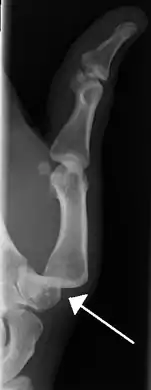

صورة شعاعية من خلع المفاصل السلامية للاصبع الصغير في اليد اليمنى